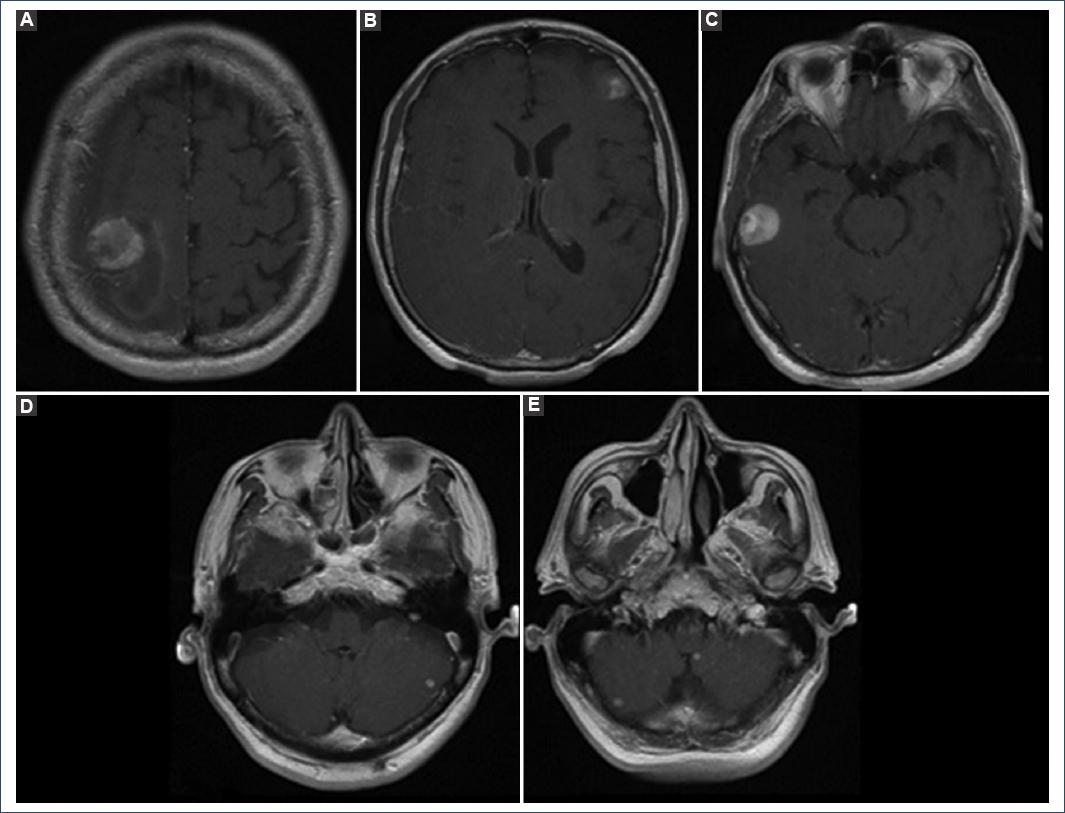

A 68-year-old male with no significant history who presents with a 1 week of evolution characterized by holocranial headache, decreased strength of the left hemibody (3/5), and epileptic seizures of focal onset that are secondarily generalized is admitted through the emergency room to the central military hospital. Treatment is started with levetiracetam 1000 mg every 12 h. Computed axial tomography and cerebral magnetic resonance imaging studies were done, which showed 6 supra and infratentorial intracranial lesions of heterogeneous intensity with enhancement ring contrast (Fig. 1).

Figure 1 Pre-operative magnetic resonance imaging in the T1 sequence in the axial section A: right frontoparietal lesion of heterogeneous intensity with ring contrast enhancement. B: left frontal lesion. C: right temporal lesion. D: lesion in the left cerebellar hemisphere. E: lesion in the hemisphere right cerebellar and left cerebellar peduncle.